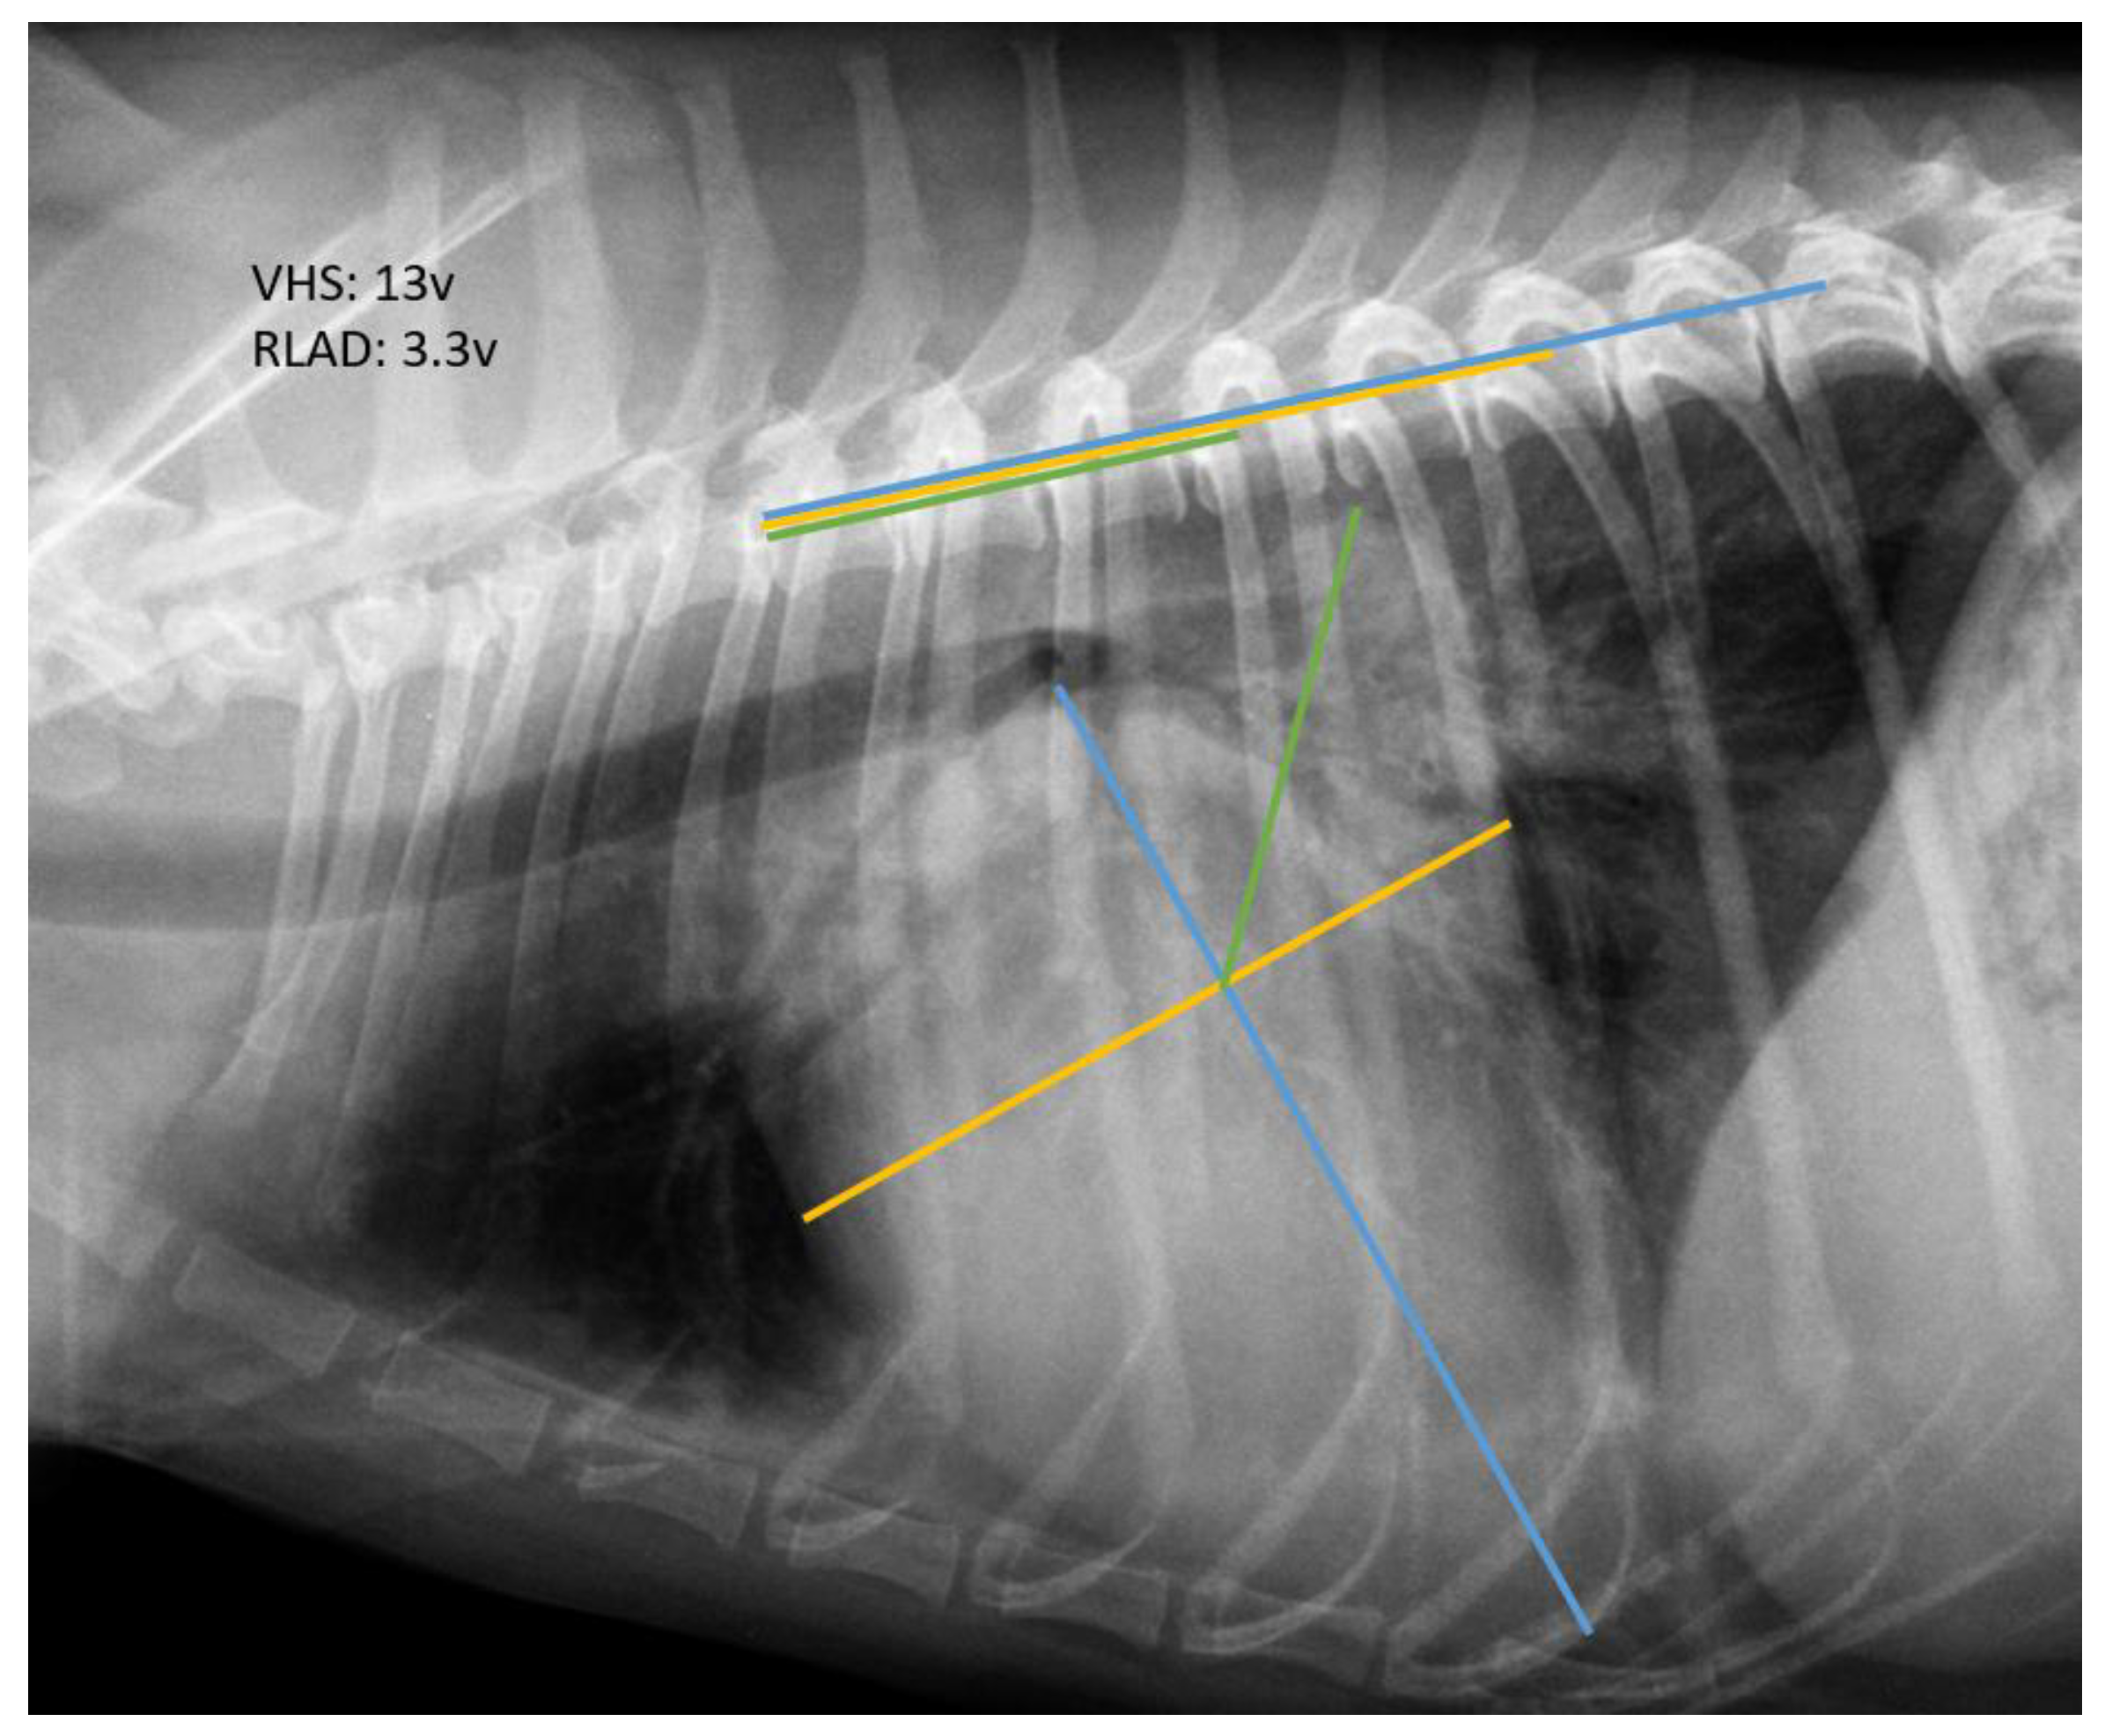

2.2. Radiographic Measurements